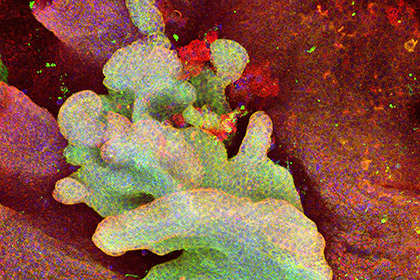

Объяснена смертоносность раковых клеток

Исследователи из Кембриджского университета впервые выявили первичную раковую клетку, иными словами, клетку, из которой вырастает злокачественная опухоль — . . . |